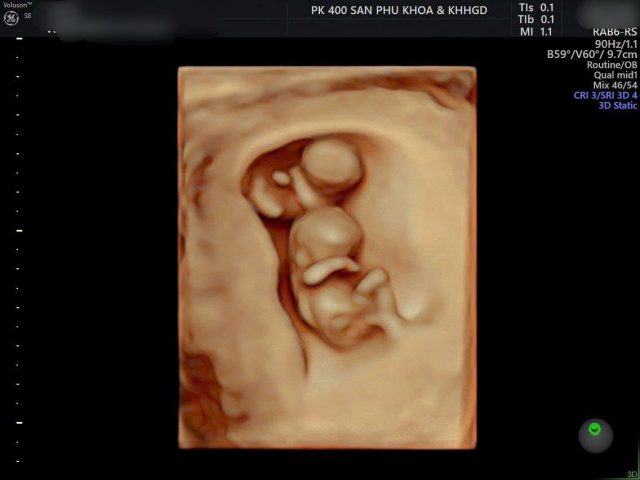

Trong một thai kỳ có hai hay nhiều thai nhi cùng lớn lên trong tử cung mẹ được gọi là đa thai. Có 2 trường hợp đa thai: Đa thai cùng trứng và khác trứng.

Mẹ bầu thường được khuyên đến bác sĩ thường xuyên hơn để kiểm soát tình trạng sức khỏe của mẹ và sự phát triển của em bé. Việc siêu âm đúng lịch cũng giúp bác sĩ sớm phát hiện các dị tật thai nhi, đồng thời phát hiện sớm những tai biến sản khoa (như tiền sản giật, hội chứng truyền máu song thai…) để có hướng can thiệp kịp thời.